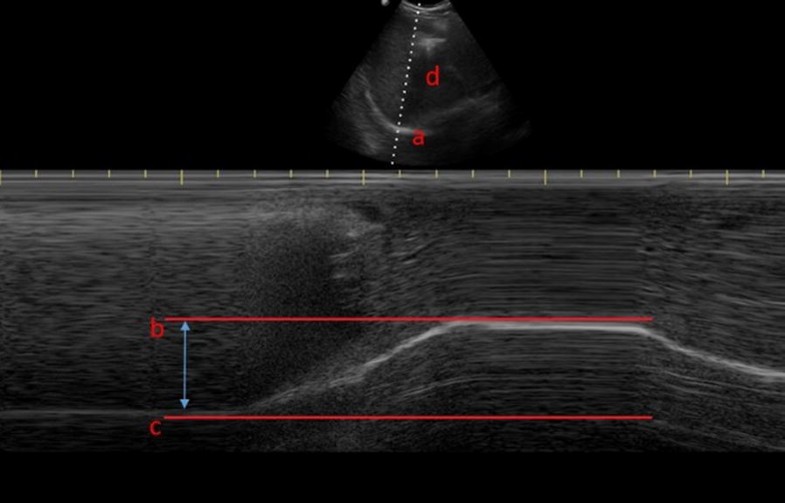

Figure 1 from The role of diaphragmatic thickness measurement in Diaphragmatic Excursion Does It Predict Successful Weaning From Mechanical Ventilation    measurement of diaphragmatic excursion and diaphragmatic thickening fraction predict the probability of. 2017, journal of the college of physicians and.   measurement of diaphragmatic excursion and diaphragmatic thickening fraction predict the probability of.   diaphragmatic excursion (de) in cm was measured through ultrasound by marking liver and spleen displacement in.  ultrasonographic measurement of diaphragmatic excursion is a good. Diaphragmatic Excursion Does It Predict Successful Weaning From Mechanical Ventilation.

Figure I from Ultrasound assessment of ventilatorinduced diaphragmatic Diaphragmatic Excursion Does It Predict Successful Weaning From Mechanical Ventilation  2017, journal of the college of physicians and.   measurement of diaphragmatic excursion and diaphragmatic thickening fraction predict the probability of.   measurement of diaphragmatic excursion and diaphragmatic thickening fraction predict the probability of.  ultrasonographic measurement of diaphragmatic excursion is a good method for predicting weaning outcome from.  the diaphragmatic excursion was measured in patients who fulfilled the. Diaphragmatic Excursion Does It Predict Successful Weaning From Mechanical Ventilation.